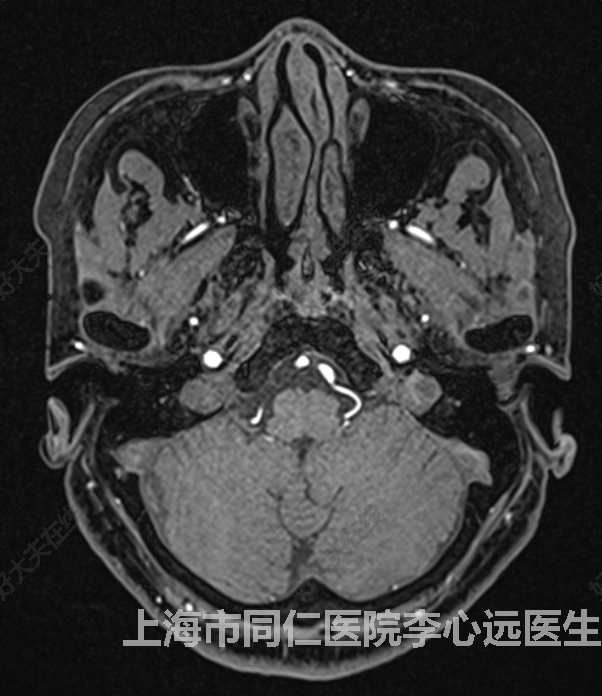

體位失能性眩暈是指在起床或者躺下的過(guò)程中,轉(zhuǎn)換體位,頭頸部屈伸和轉(zhuǎn)動(dòng)時(shí)誘發(fā)的眩暈,稱為體位性眩暈。癥狀嚴(yán)重的閉眼后仍有天旋地轉(zhuǎn)感,同時(shí)伴有惡心嘔吐、耳鳴、雙眼黑懵等,大多數(shù)患者持續(xù)時(shí)間為數(shù)十秒至數(shù)分鐘,休息后會(huì)有所緩解,反復(fù)發(fā)作,影響正常生活。眩暈是前庭核團(tuán)受到血管壓迫,血管與神經(jīng)外層相互磨損,發(fā)生短路,神經(jīng)放電過(guò)度,造成前庭神經(jīng)障礙產(chǎn)生眩暈。患者發(fā)病后常就診耳鼻喉科,常見(jiàn)病因有多種:首先考慮為耳石癥、美尼爾綜合征等,頭部位置變動(dòng)后因耳石刺激半規(guī)管引發(fā)眩暈,常通過(guò)營(yíng)養(yǎng)神經(jīng)的藥物、手法復(fù)位等治療,但大部分患者治療效果不佳。其次可能是因?yàn)榘l(fā)生體位性低血壓,如平時(shí)在蹲下、起立過(guò)程中出現(xiàn)頭暈。還有可能是中樞神經(jīng)系統(tǒng)病變,如腦干、小腦病變。頸椎病也會(huì)引起體位性眩暈,但臨床上頸椎引起的體位性眩暈較少見(jiàn)。目前有效治療體位改變性眩暈的方法有“前庭神經(jīng)微血管減壓術(shù)”,患者完善相關(guān)檢查,磁共振提示面聽(tīng)神經(jīng)旁有血管接觸,排除耳源性(比如病毒感染引起的內(nèi)耳淋巴循環(huán)、中耳炎等)、頸椎病椎動(dòng)脈型、腦缺血及腦腫瘤等原因后,一般考慮該患者由于血管壓迫橋延溝處的眩暈下級(jí)中樞引起的眩暈,術(shù)中墊開(kāi)責(zé)任血管,用Teflon墊片分隔血管與面聽(tīng)神經(jīng)、橋延溝、延髓的接觸。神經(jīng)就像是電線,前庭神經(jīng)受到血管壓迫,神經(jīng)外層與血管長(zhǎng)期相互磨擦、破損,發(fā)生短路,神經(jīng)過(guò)度放電,造成神經(jīng)傳導(dǎo)障礙產(chǎn)生眩暈。解除血管對(duì)神經(jīng)的壓迫,眩暈癥狀便會(huì)消失。?